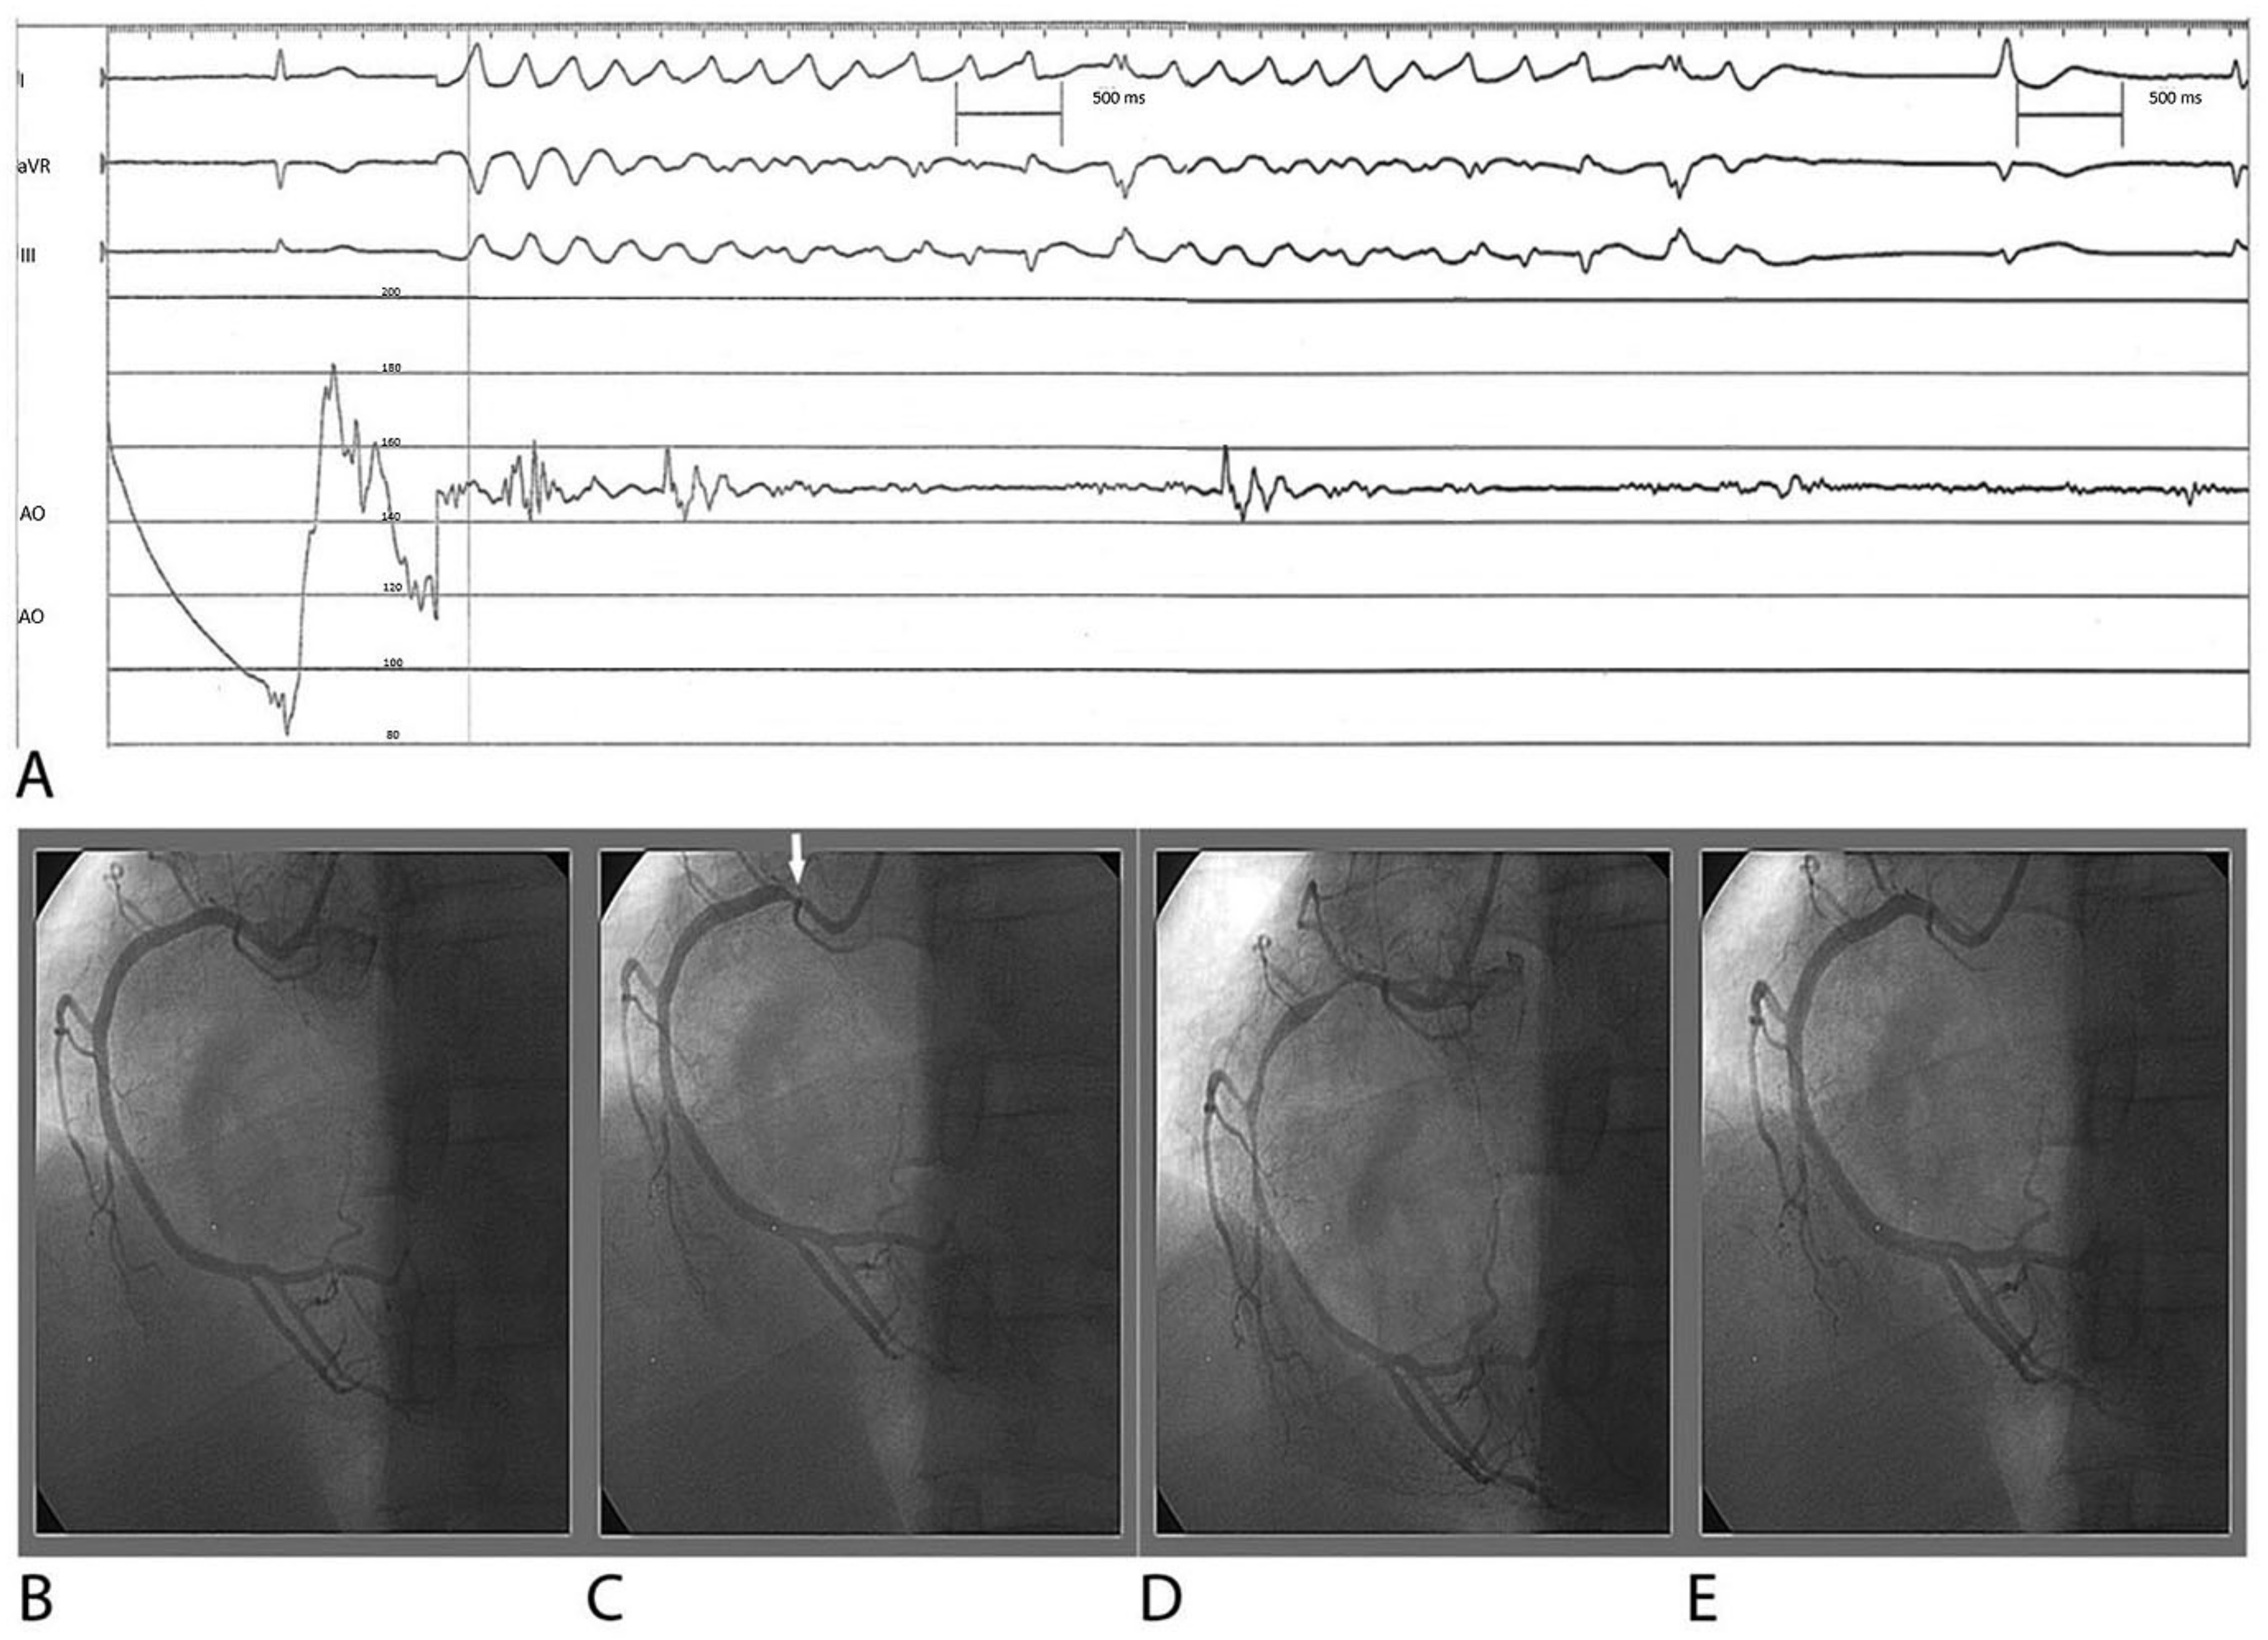

- Hung, M.J.; Cheng, C.W.; Yang, N.I.; Hung, M.Y.; Cherng, W.J. Coronary vasospasm-induced acute coronary syndrome complicated by life-threatening cardiac arrhythmias in patients without hemodynamically significant coronary artery disease. Int. J. Cardiol. 2007, 117, 37–44. [Google Scholar] [CrossRef] [PubMed]